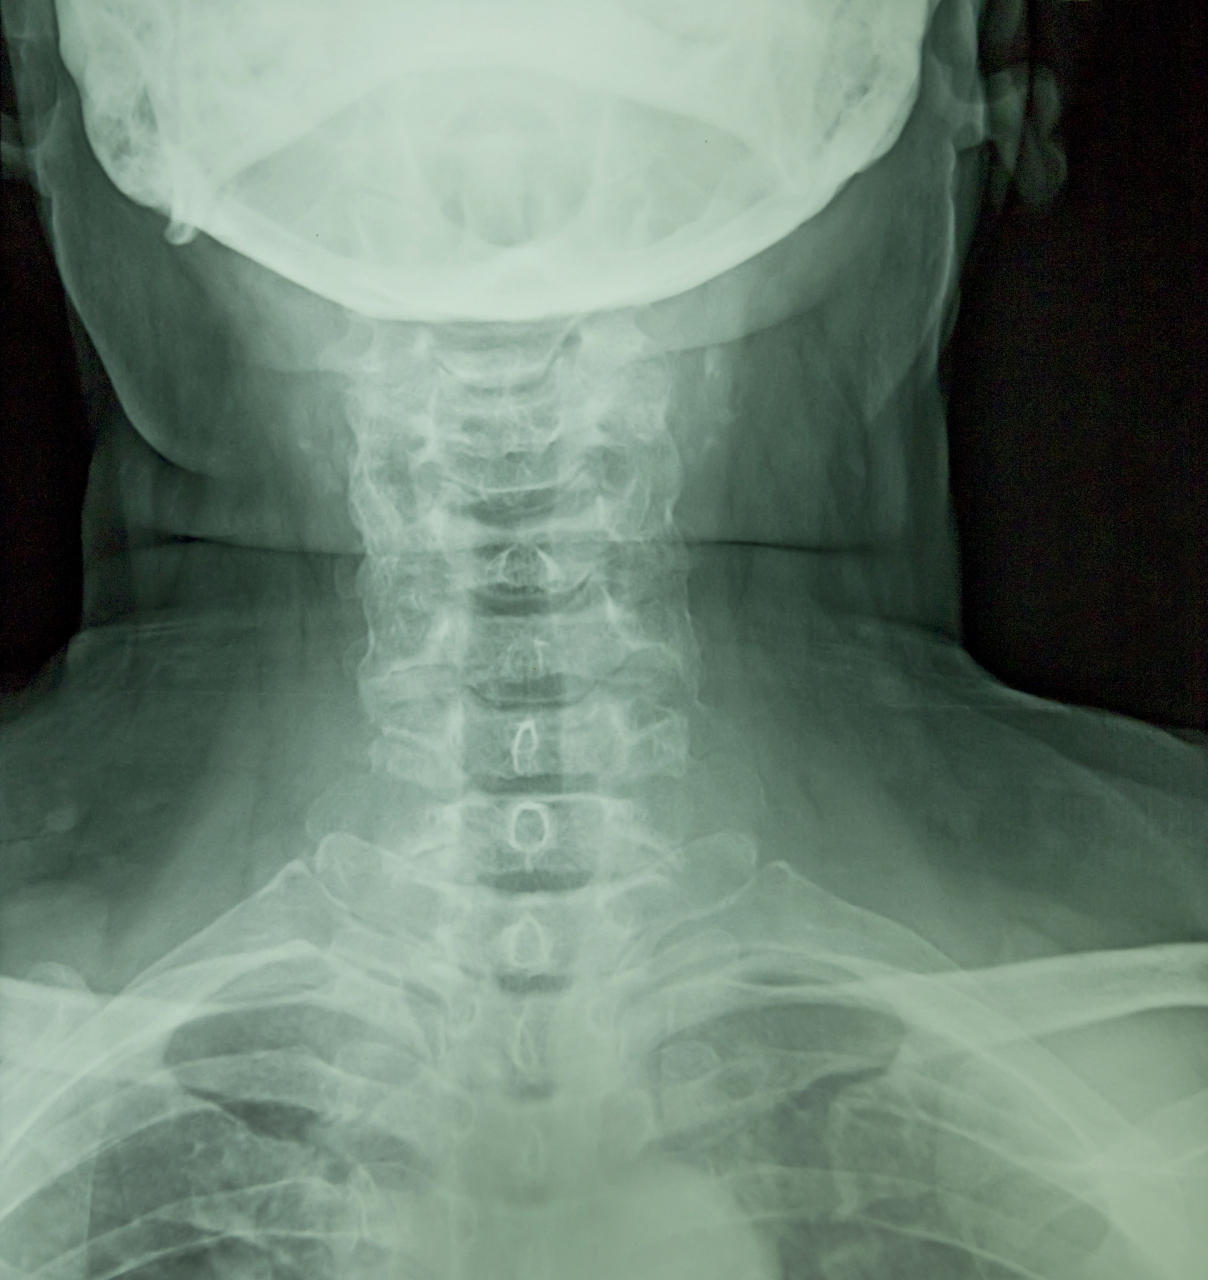

颈肋综合征

双侧颈肋并肋骨间骨性联合

颈肋可以压迫臂丛神经和锁骨下动脉图10-12 用于评价胸廓出口综合征的